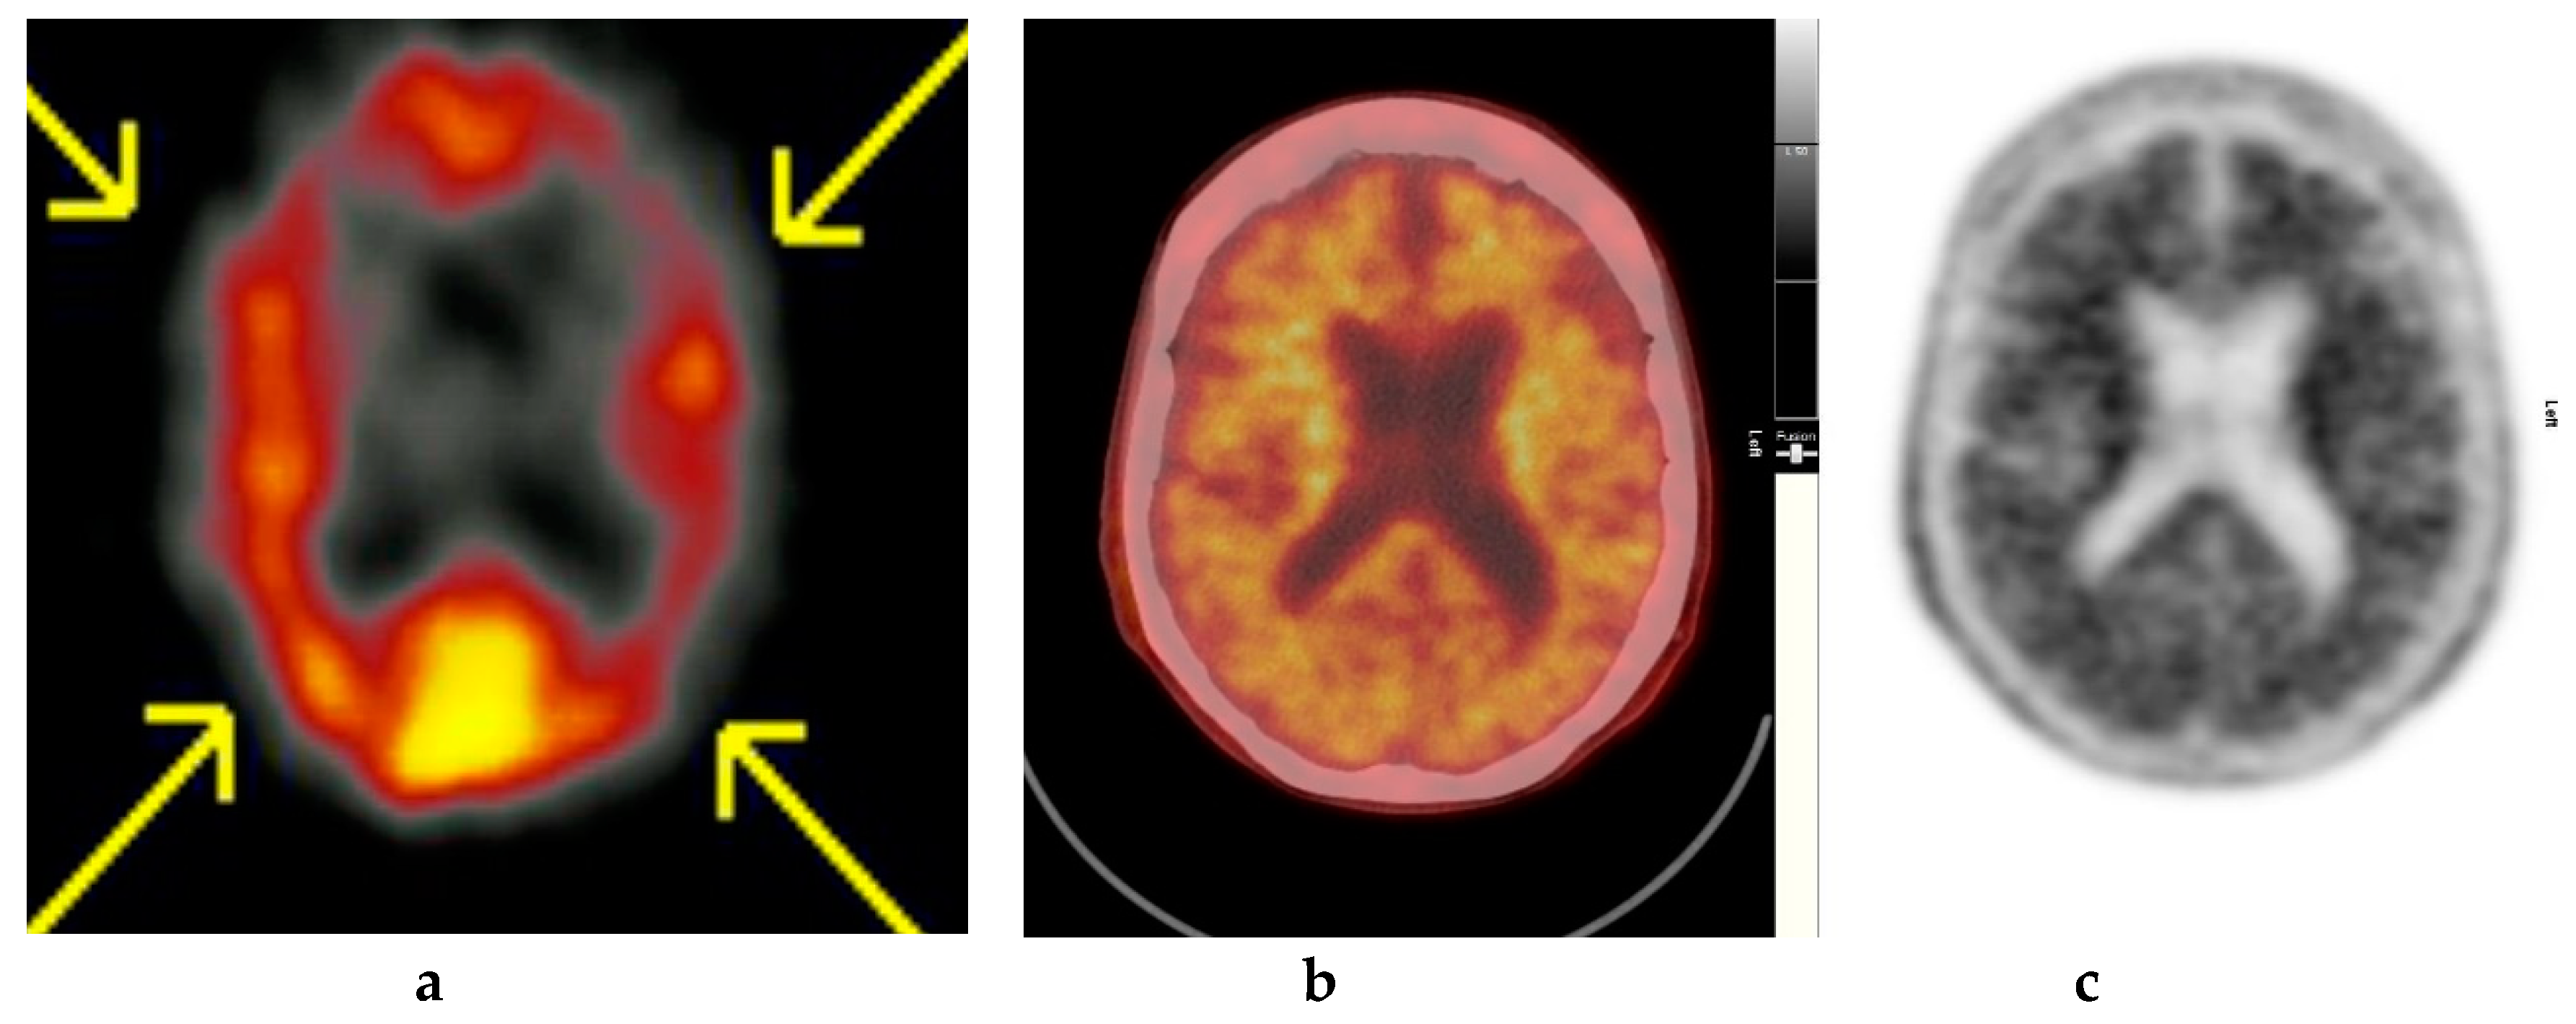

Figure 4.

Abnormal study. Sixty-eight year old female patient with speech difficulties, deficits in memory, and visuospatial abilities. (a) [99mTc]HMPAO-SPECT brain scan shows asymmetrical heterogenous reduced perfusion to both parietal and temporal lobes (worse on the left side) as with involvement of the frontal lobes identified by the yellow arrows. Normal areas of temporal perfusion were noted in between the abnormal parietal and frontal areas. In a patient with cognitive impairment, the findings indicate patterns of cerebral blood flow commonly seen in patients with mixed dementia, i.e., Alzheimer’s disease with vascular dementia. (b) Color coded [18F]FBP scan. (c) Grey scale [18F]FBP scans show loss of contrast between grey and white matter in all sections of the brain suggestive of beta-amyloid plaque deposition/disease. In conjunction with the [99mTc]HMPAO-SPECT brain scan, the overall findings are again suggestive of vascular as well as beta amyloid plaque disease (early AD), making the diagnosis mixed type AD. (Figures are courtesy RLBUHT Hospital database).